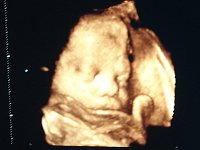

- 3D/4D Ultraschall

- Wunsch-Ultraschall